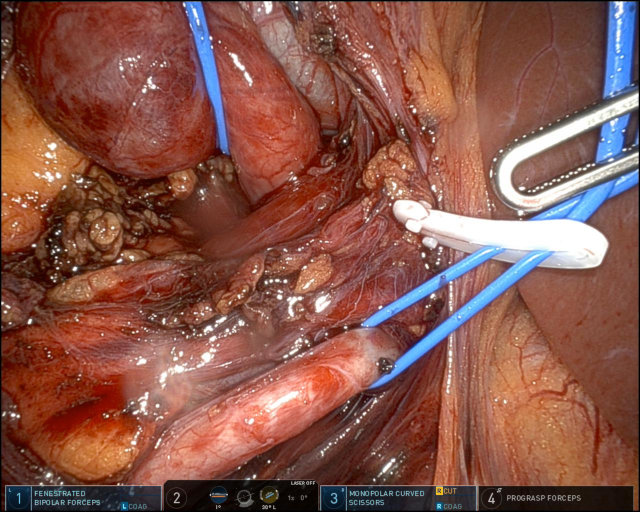

In diesem Fallbericht beschreiben wir einen 17-jährigen Patienten, der mit rez. ausgeprägten Koliken in unserer Abteilung vorstellig wurde. Initial erfolgte bei Hydronephrose °III und pos. Steinanamnese des Vaters eine CT-Abdomen nativ, welche bereits den V.a. einen retrocavalen Harnleiter rechts ergab. Eine Szintigraphie bestätigte eine urodynamisch relevante Obstruktion bei ausgeglichener Nierenfunktions. Bei Symptomatik erfolgte eine retrograde Ureteropyelographie mit JJ-Einlage. Im weiteren Verlauf wurde noch eine MRT-Angiographie durchgeführt, welche den Befund eindeutig bestätigte. Daraufhin erfolgte am 10.11.2025 die daVinci-assistierte Ureterureterostomie rechts in Linksseitenlage. Hierfür wurden 4 Arbeitstrokare und ein Kameratrokar verwendet. Die Gesamtoperationszeit lag bei 181 min, die reine Konsolenzeit bei ca. 100 min. Intraoperativ erfolgte ein JJ-Wechsel. Die Anastomose erfolgte mit einer 4.0 Quill-Naht in fortlaufender Technik. Der Blutverlust lag bei ca. 20 ml. Postoperativ waren die Schmerzen mit Novalgin gut beherrschbar. Die Entlassung erfolgte am 5. postoperativen Tag nach DK-Entfernung.

Die robotisch assistierte Operation eines retrocavalen Harnleiters stellt unserer Meinung heutzutage den Goldstandard dar. Die Operation kann sicher und mit sehr niedrigem Risiko durchgeführt werden. In der Literatur liegen die mittleren OP-Zeiten für die Laparoskopie über denen für die robotische Rekonstruktion, ebenso ist der Blutverlust für die robotische Technik niedriger. Eine offene Operation sollte heutzutage bei diesem Krankheitsbild möglichst vermieden werden.

Abbildung 1 [Abb. 1], Abbildung 2 [Abb. 2], Abbildung 3 [Abb. 3], Abbildung 4 [Abb. 4], Abbildung 5 [Abb. 5], Abbildung 6 [Abb. 6], Abbildung 7 [Abb. 7], Abbildung 8 [Abb. 8], Abbildung 9 [Abb. 9], Abbildung 10 [Abb. 10]